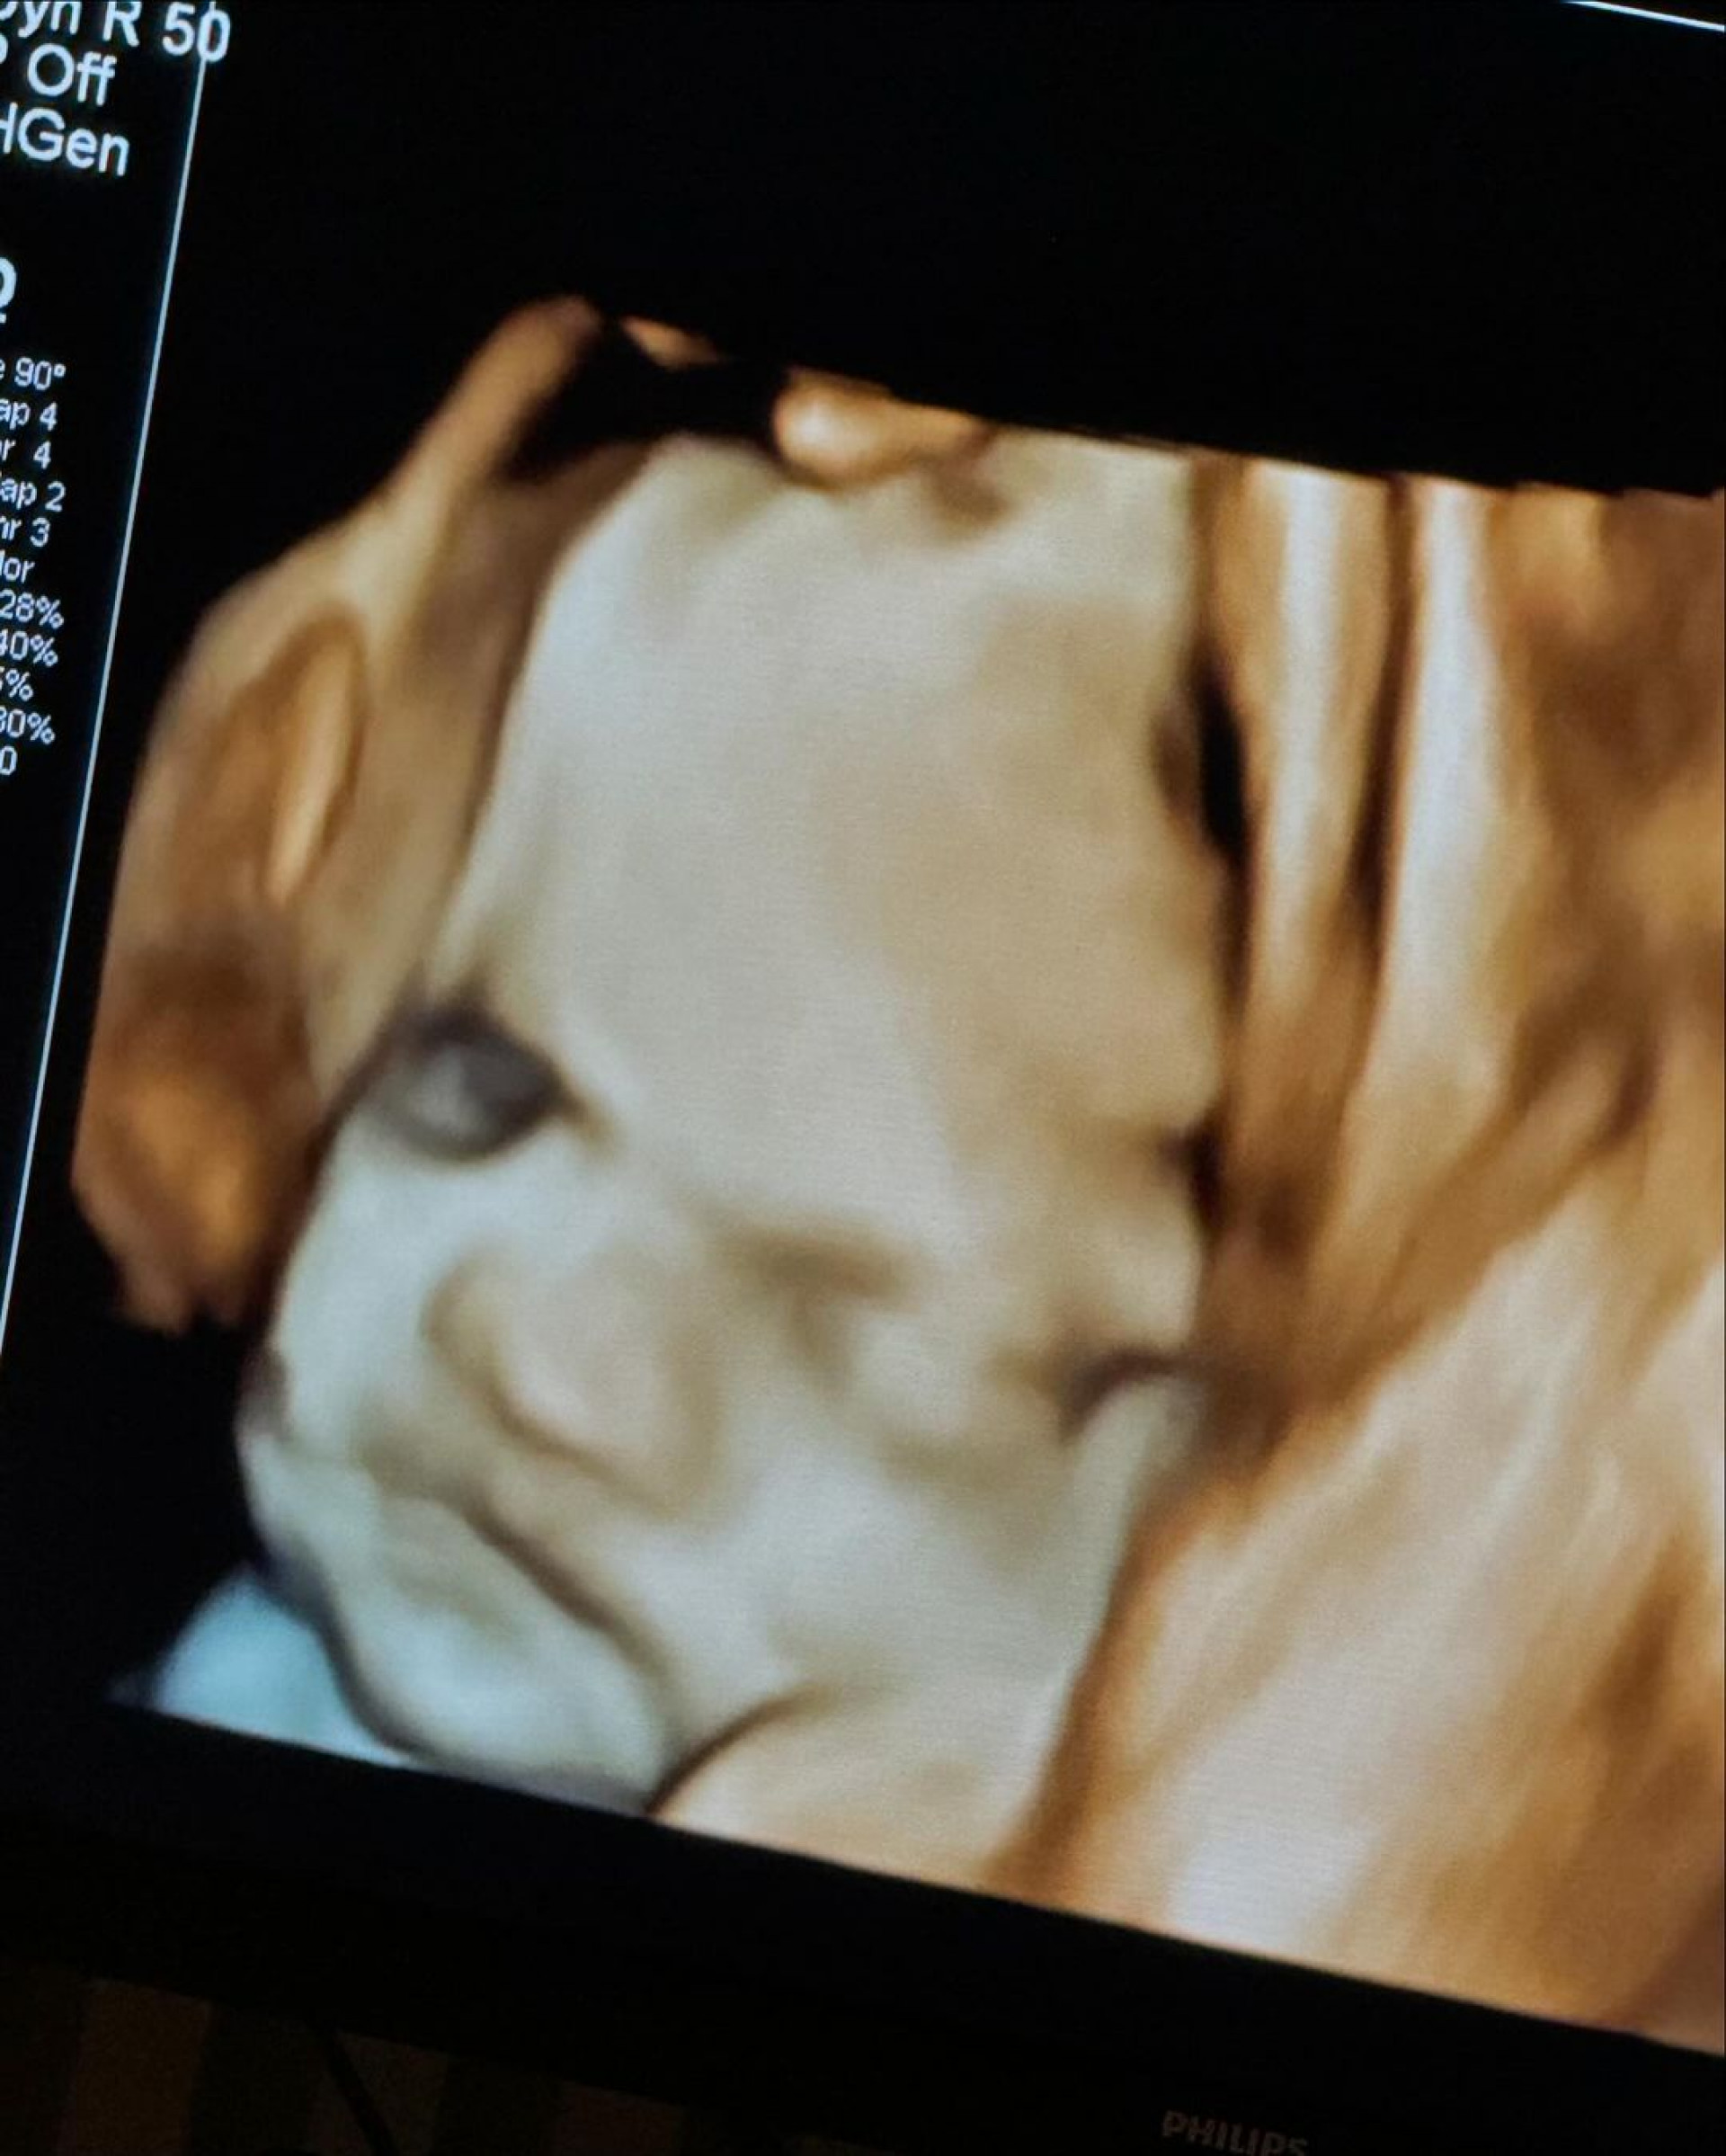

Virginia Fonseca mostra ultrassom do terceiro filhoReprodução

Rio - Grávida, Virginia Fonseca compartilhou, nesta sexta-feira (28), imagens do ultrassom de seu terceiro filho, José Leonardo, fruto de seu relacionamento com Zé Felipe. Em seu Instagram, a influenciadora falou sobre a expectativa da chegada do pequeno e revelou que tem o achado parecido com a filha, Maria Flor, de 1 ano.

"Meu Deus! Conseguimos ver um pouquinho do rostinho do Zé Leonardo. Eu estou achando ele a cara da Floflo (risos). Ô mãezinha, estou ficando ansiosa para te ver totoco. Que você venha com MUITA saúde e que Deus abençoe sua vida sempre, amém", escreveu na legenda da publicação.

Nos comentários, os internautas repercutiram a semelhança entre os filhos do casal, que também são pais de Maria Alice, de 2 anos. "Mas gente, a Maria Flor está ficando a cara da Maria Alice… Daqui a um tempo os três vão parecer muito", disse uma seguidora. "As imagens desses ultrassom são muito engraçadas, mas lembra a Floflo mesmo", afirmou outra. "Eu achei parecido um pouco com a Maria Alice", opinou uma fã.